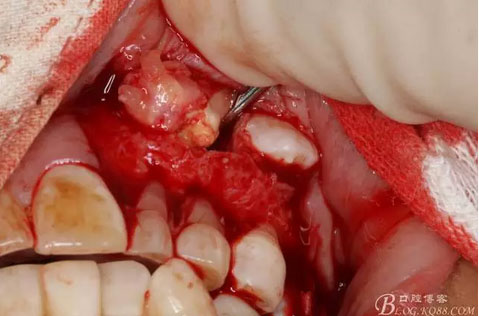

圖13.暴露出部分牙瘤

圖15.剝離出來的多個成型小牙齒及致密鈣化物。